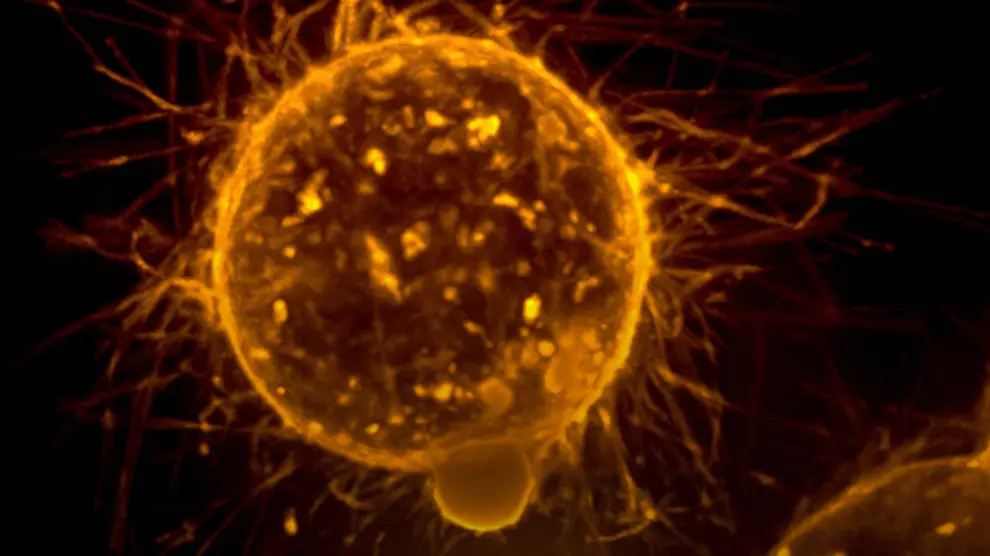

Las metástasis son responsables de más del 90 % de las muertes por cáncer, pero hasta ahora existen muy pocas terapias específicas para evitarlas.

El protagonista es el fármaco RA08, desarrollado por el VHIR y la empresa biotecnológica BCN Peptides, que actúa como inhibidor de una proteína, la integrina alfa9 (ITGA9), que es clave en el desarrollo de metástasis.

En ratones, los investigadores han observado que entre el 50 y el 70 % de los animales medicados no desarrollaban metástasis de dos de los cánceres infantiles más frecuentes: neuroblastoma, que ocurre cuando aparecen tumores en el tejido nervioso, y rabdomiosarcoma, cuando se originan en tejidos blandos, como los músculos.